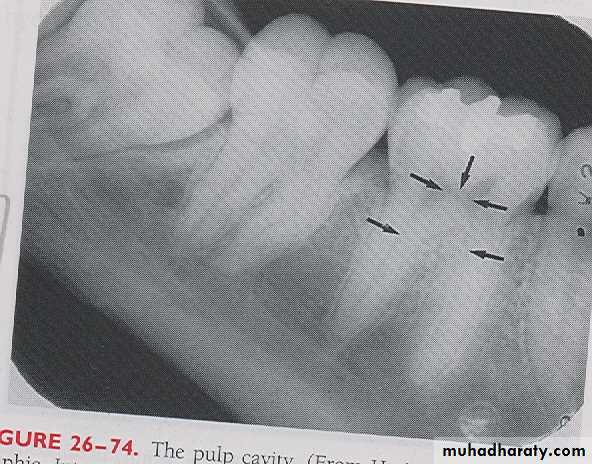

PULP CAVITY: The pulp cavity consist of a pulp chamber and pulp canals, its contain blood vessels, nerve and lymphatic and appears relatively radiolucent on dental radiograph.